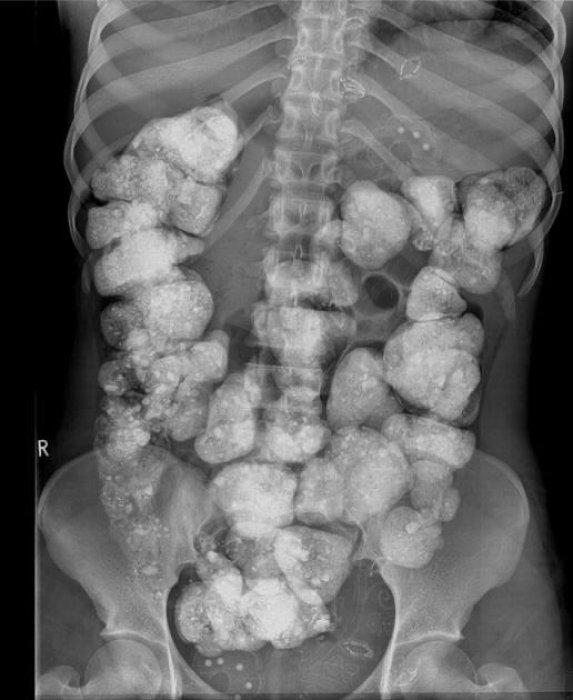

Интересный рентген. Фото: threads

На самом деле на картинке случай геофагии – это умышленное употребление земли, почвы или глины. Хотя геофагия может наблюдаться в контексте разных культурных или религиозных традиций, ее также обнаруживают у пациентов с поведенческими расстройствами или психическими заболеваниями.

Однако пользователи не смогли пройти мимо и смешно, метко и весело прокомментировали этот случай.